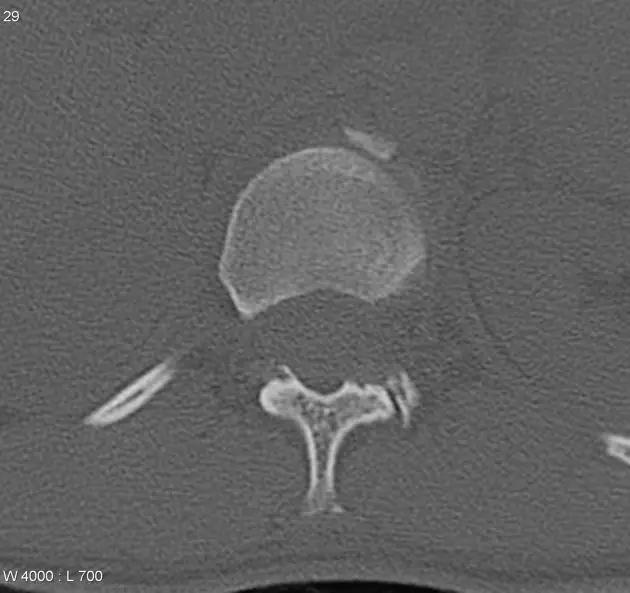

第一颈椎双侧性前、后弓骨折,X 线片上很难发现骨折线,有时在正位片上看到 C1 关节突双侧性向外移位,侧位片上看到寰椎前后径增宽及椎前软组织肿胀阴影,CT 检查最为清楚,而 MRI 检查智能显示脊髓损伤情况。

A 图是稳定的 Jefferson 骨折(横韧带完整)轴位像。B 图是不稳定的 Jefferson 骨折(横韧带撕裂)轴位像